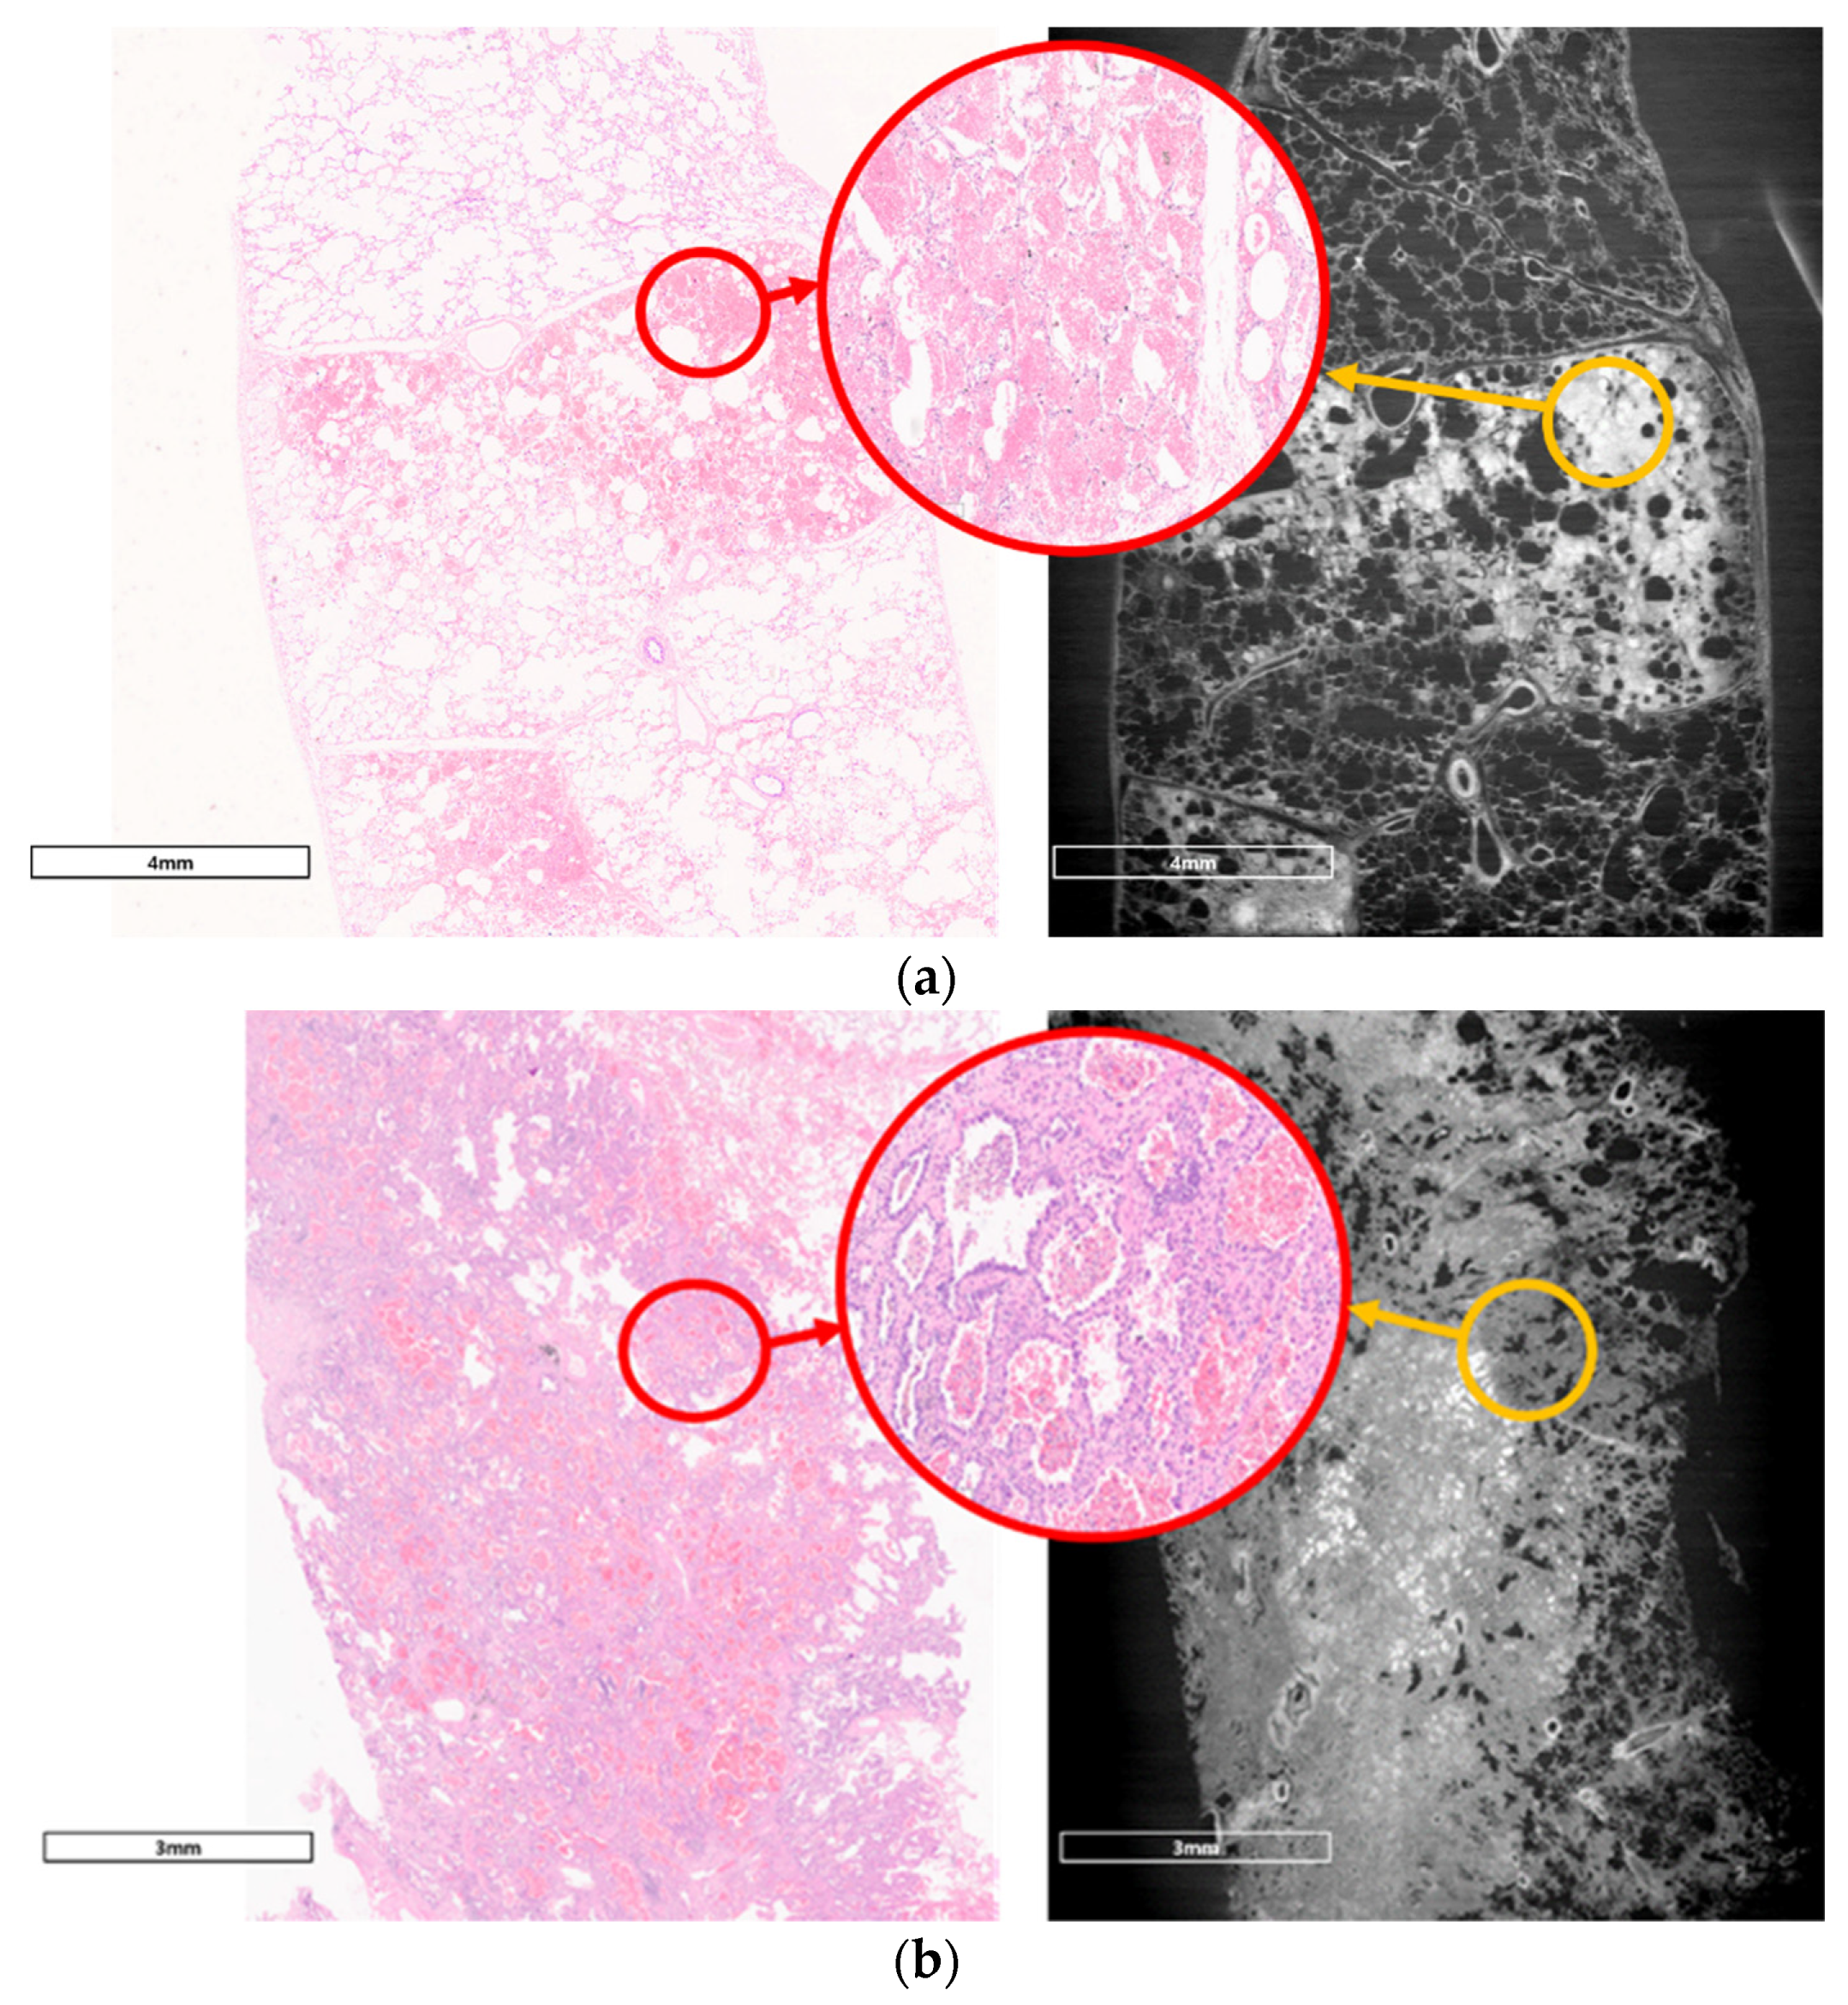

3.2. Comparison with Pathologic Examination